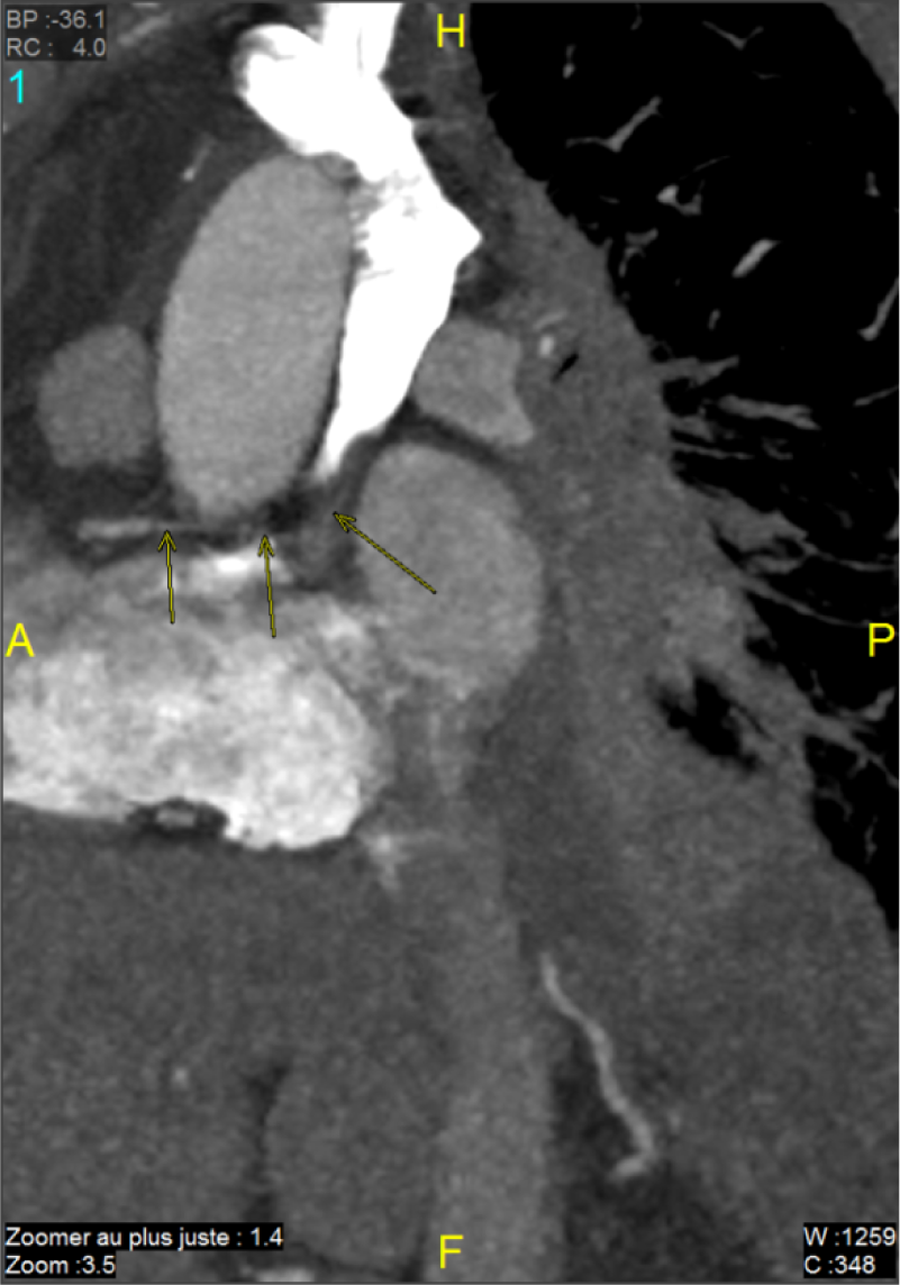

Immunotherapy was continued. The latest tumor assessment in January 2022 showed a stable disease. We asked the radiologists to perform a CT scan to determine the site of the fistula (Figures 2, 3).

Figure 2

Sagittal section: the path of the ectopic bronchial artery (coroscan).